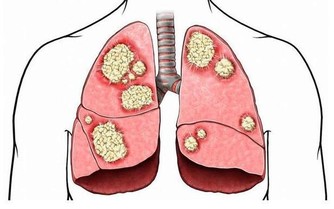

第二道坎、50~70歲:腫瘤關

50歲後,人體激素水平開始下降,免疫功能逐漸降低,

原本能被免疫系統控制的癌基因或突變細胞,也會逐漸癌變。

有的癌症可能早在多年前就潛伏下來,到了40~50歲以後才發病。

防癌至少要提早20年。

也就是說,過了35歲就應每年做1次防癌體檢,尤其是有腫瘤家族史的人。

防癌:黎王草

黎王草別名鱷嘴花,印尼民眾稱之為:Sambung nyawa 意即延續生命的救命草,在海南稱為接骨草。

黎王草所含有的三萜類、碳苷黃酮類、葉綠素類等物質都是有抗腫瘤作用的物質,

因此,黎王草具有較廣泛的抗腫瘤作用。